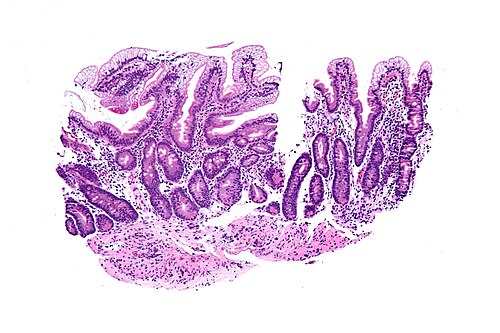

6 month old boy, chronic diarrhea

Duodenum.

Intermediate magnification. H&E stain.

Delayed motor development. Mild anemia. Low triglyceride. Low cholesterol. Low LDL. Low HDL. Low apolipoprotein A and B.